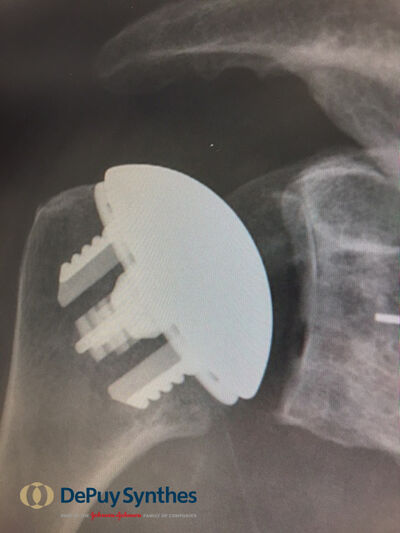

- Die Schulterkappenprothese:

- Die anatomische Schultergelenksendoprothese mit Schaft und Ersatz der Gelenkpfanne

- Die inverse Schultergelenksendoprothese: